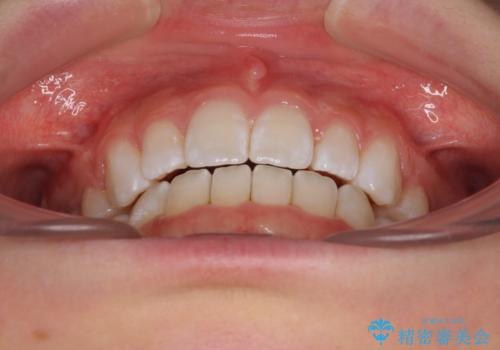

【モニター】口が閉じにくい 膨らんだ口元を抜歯矯正ですっきりと

- 前歯の出っ歯と口元の閉じにくさを気にして来院された患者様です。

口元を積極的に引っ込めるために、上下左右の小臼歯4本を抜歯することとしました。

4本の歯を抜歯したことで、飛び出していた口元が引っ込み、横顔が大きく改善されました。